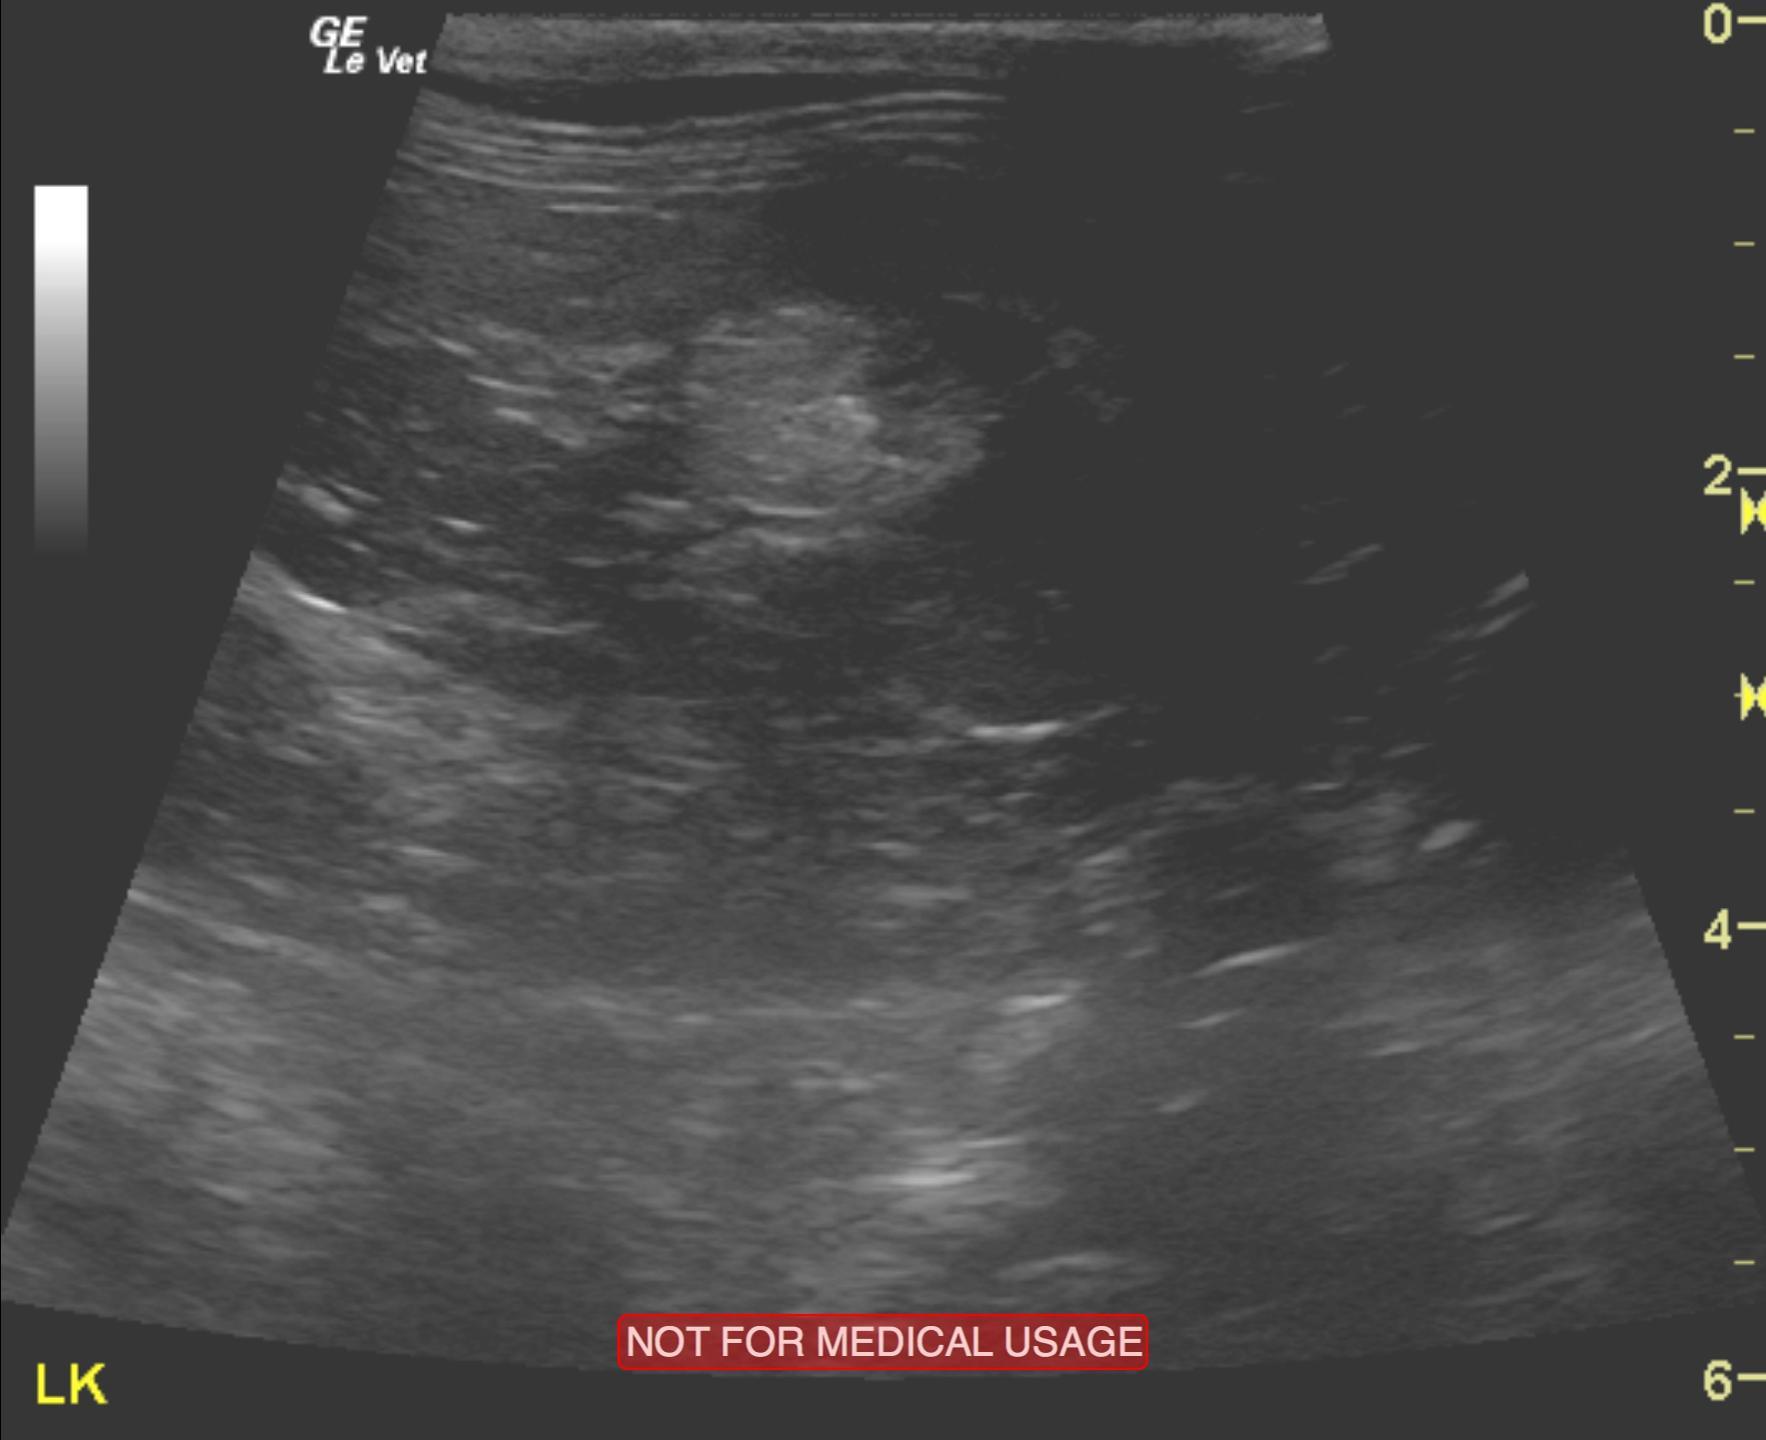

A 5-year-old male neutered DMH cat was presented for evaluation of PU/PD, abnormal behavior, and inappropriate urination (periuria). Low-normal specific gravity (1.014) was evident on urinalysis. CBC was within reference range, but serum biochemistry revealed azotemia.